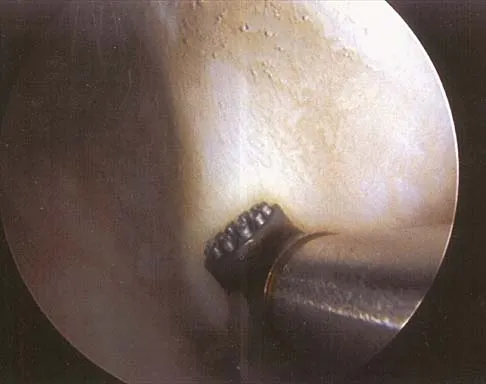

Figure 4a shows the radiograph of a 20-year-old man who has an injury to the right shoulder. Figure 4b shows an arthroscopic view (posterior portal). The arrow points to a

Explanation